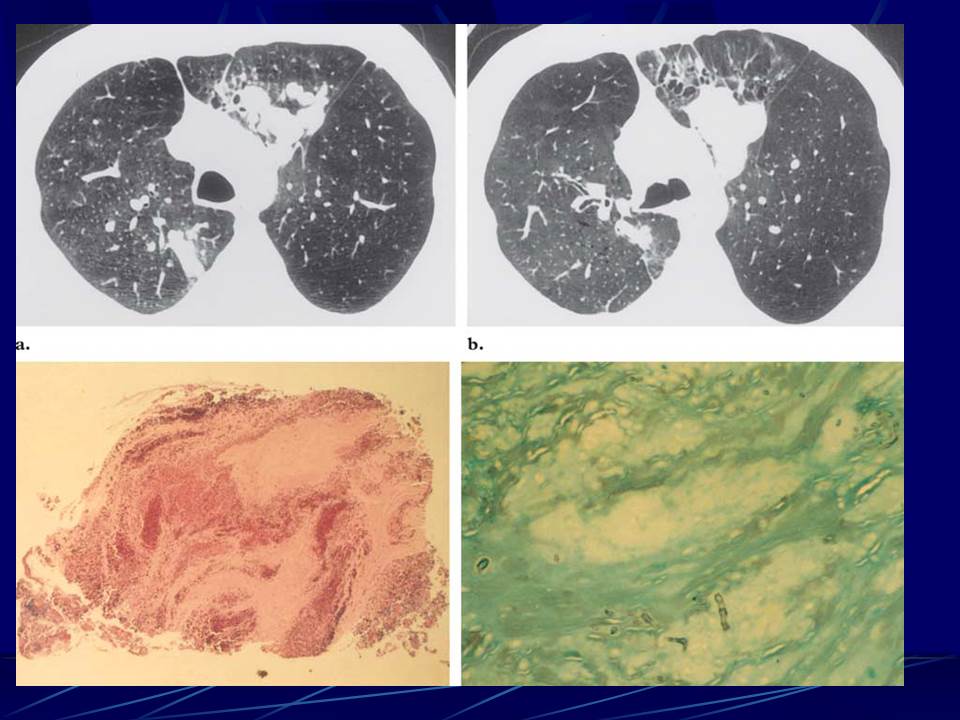

肺部真菌感染影像学分析